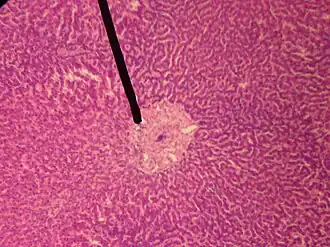

A single lobule of the liver of a pig. X 60. (Central vein not labeled, though region is visible. Central vein would be a single vein at the center of the lobule.)

In microanatomy, the central vein of liver (or central venule)[1] is a vein at the center of each hepatic lobule.[2] It receives the blood mixed in the liver sinusoids to drain it into hepatic veins.[3]